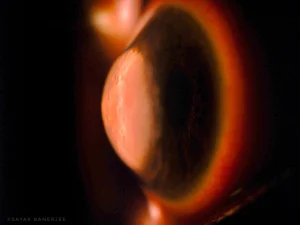

| The moon’s surface or a cornea’s story | Captured with a Topcon SL D701 using the Sclerotic Scatter technique, this image reveals the essence of a keratoconic eye with hydrops. The light scatters across the cornea like the rugged surface of the Moon, while the ethereal halo in the background echoes Saturn’s majestic rings, revealing beauty even in distortion. |